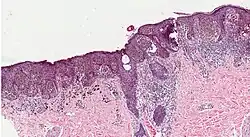

Melanoma in skin biopsy with H&E stain – this case may represent superficial spreading melanoma. -